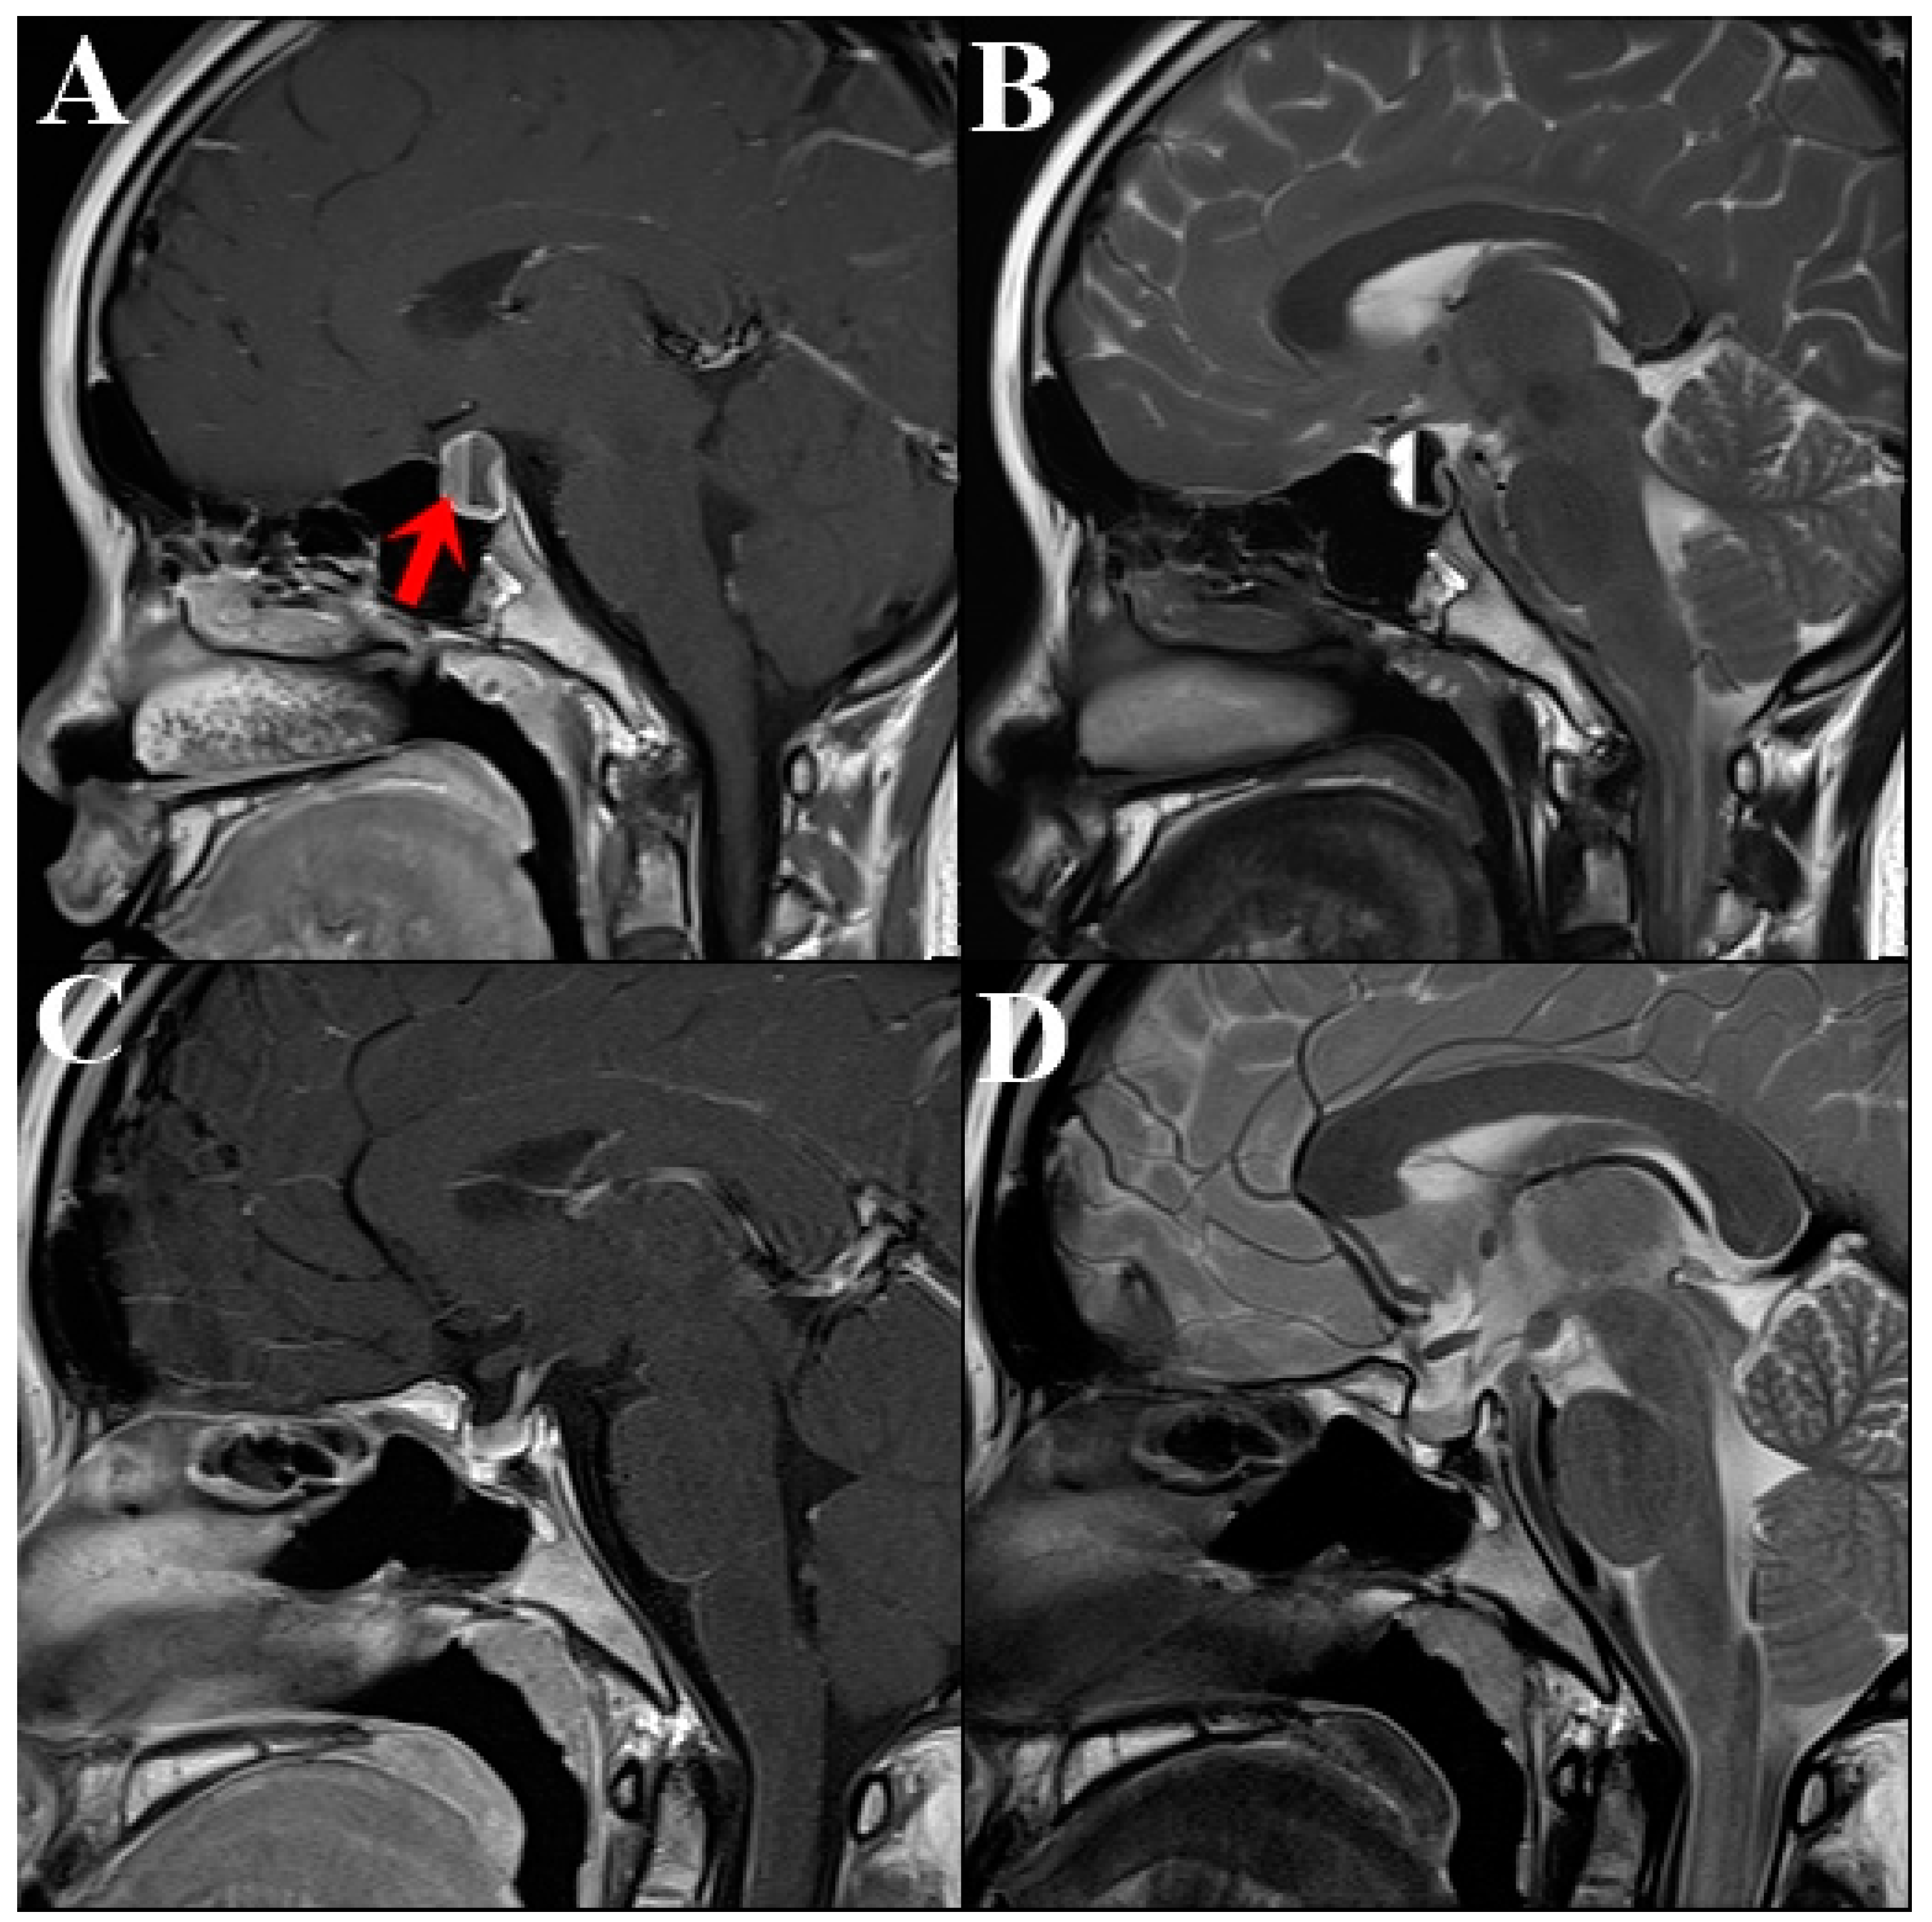

2. Case Description